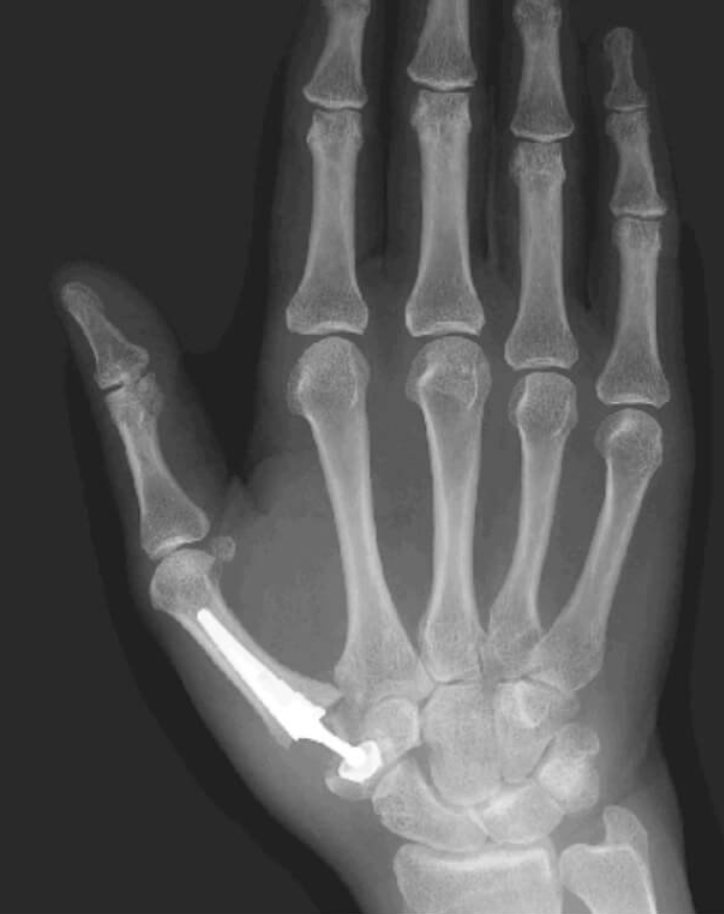

Nos casos mais avançados, a cirurgia mais realizada é a retirada do trapézio (trapeziectomia), associada ou não à reconstrução ligamentar. Técnicas como a de Burton e Pellegrini utilizam tendões para estabilizar o polegar após a ressecção óssea.

A artrodese pode ser indicada em pacientes mais jovens e com alta demanda, oferecendo maior força, porém com perda de movimento. Já as próteses são menos utilizadas devido à variabilidade dos resultados.